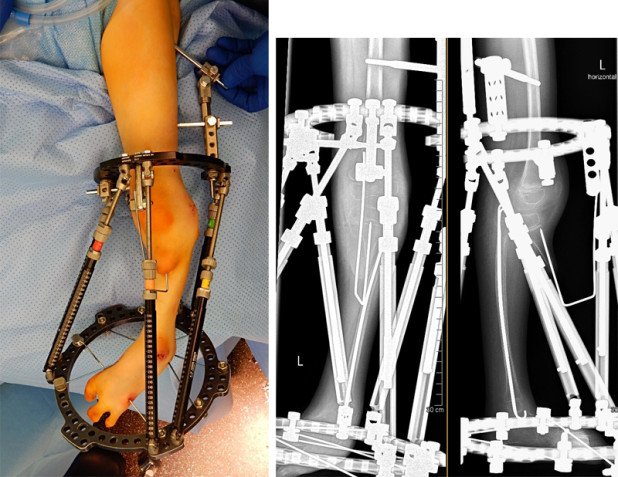

In diesem Fall fehlt das Schienbein bis auf einen kleineren Anteil am Kniegelenk. Das Wadenbein ist jedoch weitestgehend normal entwickelt. Problematisch war bei diesem Mädchen aber auch der um 90 Grad fehlgestellte Fuss. Nach der Entscheidung für eine Rekonstruktion der Extremität mit dem Kind und den Eltern haben wir zunächst einen äusseren Fixateur (Taylor Spatial Frame) implantiert. Anschliessend haben wir über drei Monate die Weichteile distrahiert (gestreckt) und damit gleichzeitig computerassistiert den Fuss in eine korrekte Stellung gebracht.